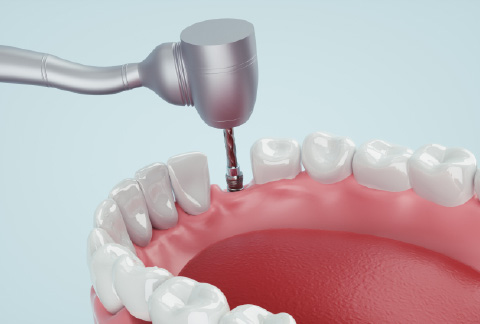

2- 一次手術

ふじなわ歯科医院では、仮歯用のインプラントを埋入することによって、本インプラントが定着するまでの期間、歯がなかったり入れ歯を入れることなくお過ごしいただけるようにしております。

※仮歯用インプラントの制作や埋入には別途料金は頂いておりません。

※骨の状態によっては仮歯用インプラントの埋入が出来ない場合もございます。